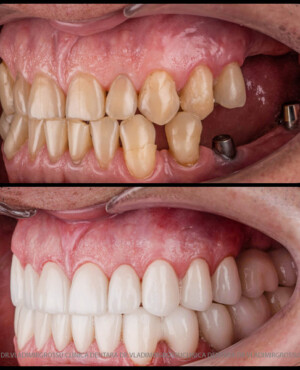

Protezarea pe implanturi dentare este soluția modernă, estetică și funcțională pentru înlocuirea dinților lipsă. Această procedură combină precizia chirurgicală cu tehnologia avansată de laborator pentru a reda pacienților zâmbetul natural, vorbirea clară și capacitatea de a mânca fără restricții.

La Clinica Dentară Dr. Grossu din Chișinău, oferim protezări pe implanturi dentare personalizate, realizate de o echipă multidisciplinară, cu ajutorul celor mai noi tehnologii digitale și materiale biocompatibile.

- Estetică superioară – imită perfect dinții naturali